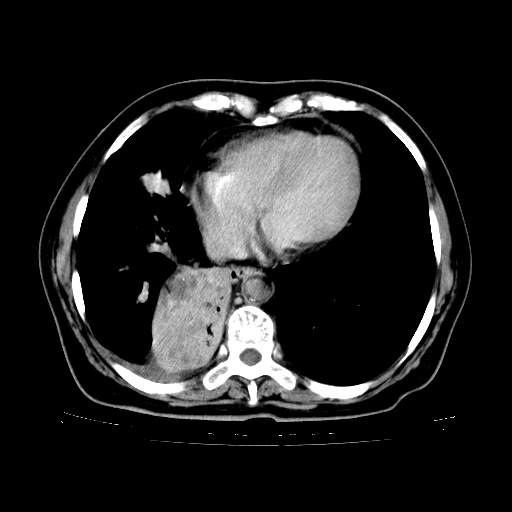

女,70岁,咳嗽、咳痰一个月,低热一周。

继发型肺结核,右下肺支气管内膜结核.右侧少量胸腔积液.主动脉夹层.

支气管内膜结核肺内播散.右侧少量胸腔积液.主动脉夹层.